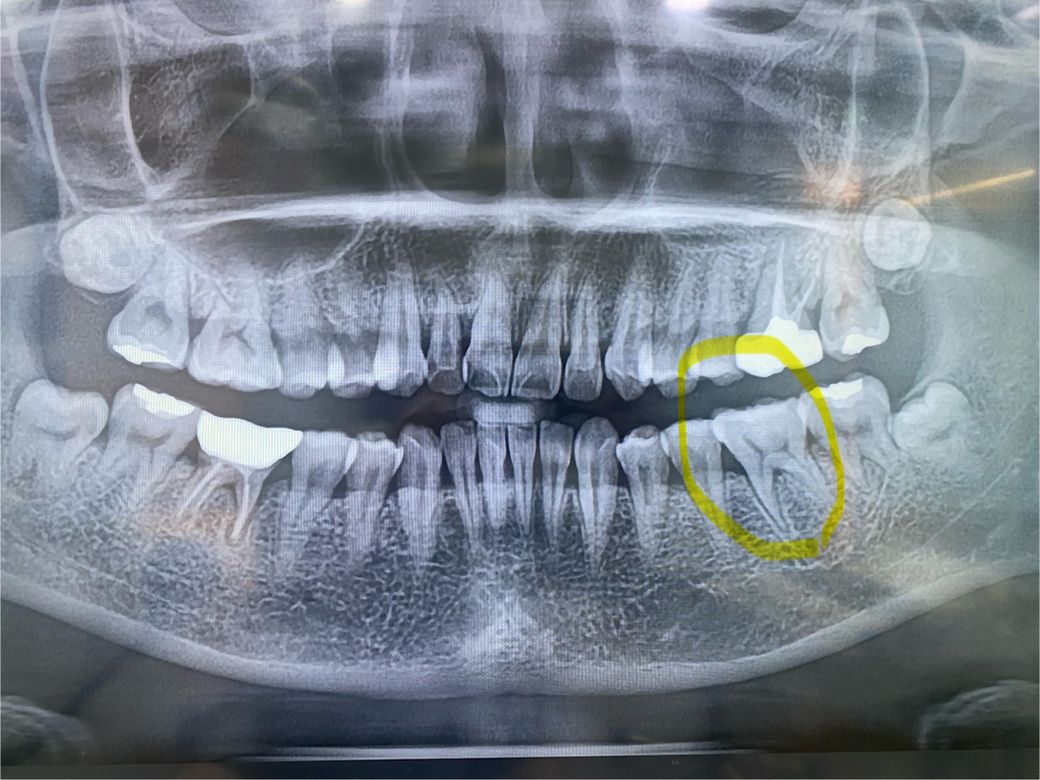

엑스레이

사진으로 보이는 충치는 깊어 보이지가 않습니다. 사진과 같은 충치를 치료해서 신경이 영향을 받을 가능성은 매우 작을 것으로 생각됩니다. 교합 간섭이 있는 경우에 시린 증상이 있을 수 있기 때문에 이런 경우에는 높이를 조정해 줄 수도 있습니다. 자세한 확인을 위해서 치과에서 진료를 받아오는 것을 권해드립니다.